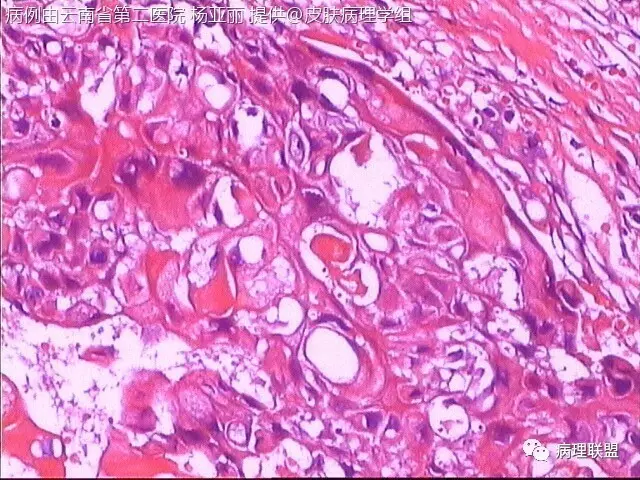

M/53 左手食指包块(皮肤鳞癌VS转移性鳞癌)

请各位老师帮忙看看,男性,53岁,左手食指包块 (病例由云南省第二医院 杨亚丽 提供,致谢!)

鳞癌没有问题。问题是否是转移癌:有否与表皮相连,病史演变如何?

@邓永键 谢谢邓主任,据说病人鼻子上有肿瘤才来切的手上的小包块,右手有,左手也有三四个,等我再问问鼻子上的是什么。看着细胞异型不明显,生长方式倒是确实不好。第6图有和表皮的关系,不相连,邓老师,鼻子上的肿瘤确实是鳞癌,这么说来手上的是转移的就很合理了。邓主任真是高,佩服!